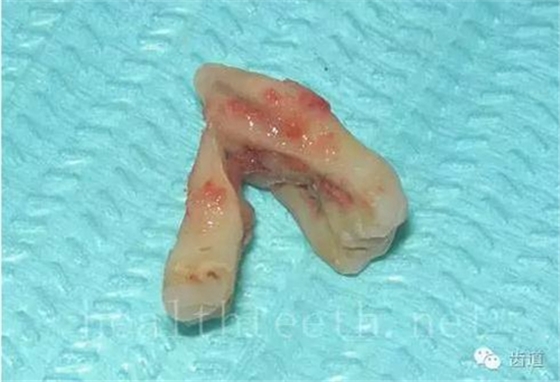

因?yàn)楸旧聿桓阏衬げ。占降牟±邢?,大多是同事收?/span> 頰粘膜扁平苔蘚 舌粘膜扁平苔蘚 舌緣創(chuàng)傷性潰瘍 長期戴活動義齒不當(dāng)或是戴不良修復(fù)義齒造成的口腔粘膜潰瘍,應(yīng)該引起高度警惕,因?yàn)檫@種潰瘍?nèi)菀装┳?/span> 黑毛舌 舌息肉,該患者同時伴有胃、食管息肉,后來看內(nèi)科了,具體情況不詳 四、孩子的牙齒問題 乳牙未退,牙根穿出牙齦對上唇粘膜造成刺激 乳牙滯留,也是孩子在退牙過程中最容易遇到的問題 五、牙齒發(fā)育上的問題 變色牙 氟斑牙 釉質(zhì)發(fā)育不全 四環(huán)素牙 牙神經(jīng)治療后的牙齒變色 10歲孩子剛剛萌出的牙齒變色 2、埋伏牙 左上乳3滯留,恒3未見萌出,曲面斷層片顯示牙齒埋伏 通過CT片確定埋伏牙齒具體的位置,顯示距離左側(cè)上頜竇很近,偏唇側(cè),這為手術(shù)定位提供了方便 手術(shù)中切斷、完整拔出,未損傷上頜竇 其他埋伏牙 3、多生牙 病例1 病例2 病例3,同時多生兩顆牙齒 4、各種畸形牙 畸形過小牙 融合牙:恒牙和乳牙都可以發(fā)生融合的情況(兩顆牙齒長在了一起) 畸形中央尖:在牙齒的中央,兩個牙尖之間又多長出一個牙尖,由于進(jìn)食的磨耗很容易造成磨穿,神經(jīng)就會與外界相通,出現(xiàn)牙髓炎的癥狀 六、牙齒的外傷 牙冠折斷 牙根折斷 烤瓷牙打樁修復(fù)后牙根折斷 外傷后牙齒的全脫位,應(yīng)該保留牙齒盡早做再植手術(shù) 七、牙齒的慢性損傷 牙頸部楔狀缺損 牙冠劈裂及完整拔除后的情況 牙根縱裂及拔除后的情況 牙隱裂,牙齒表面有肉眼看不到的裂紋,細(xì)菌通過其進(jìn)入牙髓,容易出現(xiàn)牙髓炎癥狀,嚴(yán)重可以造成牙齒的劈裂 這是一位來中國學(xué)習(xí)的俄羅斯大學(xué)生的牙齒,已經(jīng)做過了根管治療,牙齒咬合面有隱裂,通過鋼絲結(jié)扎固定,做鑄造金屬冠修復(fù)。 八、牙髓炎、根尖周炎 下面圖片都是慢性根尖周炎的病例,有了齲齒,進(jìn)一步發(fā)展就是牙髓炎,如果此時沒有得到及時的治療,疾病會逐漸發(fā)展破壞到根尖的骨質(zhì),將骨質(zhì)破壞后就在牙齦上出現(xiàn)一個膿瘺,此時患者不再感覺到牙齒的疼痛了,往往忽視了治療,但是這種不痛并不是疾病好轉(zhuǎn)了,而是因?yàn)榧膊〉难仔詽B出得到了引流,這個膿瘺會出現(xiàn)有時候變大了,有時候又變小了,但是如果不治療是不會自己愈合的,只有經(jīng)過完善的根管治療后才有好轉(zhuǎn)的可能,但是在疾病的治療中時間是起決定作用的,時間拖得越晚,好轉(zhuǎn)的可能性越小,經(jīng)過根管治療后如果膿瘺還是沒有消失,就需要做根尖刮治術(shù),如果仍然沒有好轉(zhuǎn),就只能做根尖切除術(shù)了,這對牙齒的穩(wěn)固是不利的。下面圖片中在膿瘺中插入了一個牙膠尖,是我們做根管充填用的材料,是非常軟的,就是在口腔牙齦瘺管的地方插進(jìn)去,通過拍牙片可以清晰地看到它到達(dá)的位置,從而確定發(fā)病的牙齒,此處是為了讓大家看得更清楚。 門牙兩個膿瘺 烤瓷牙修復(fù)后牙齦出現(xiàn)兩個膿瘺,插入牙膠尖,牙片顯示牙膠尖到達(dá)的位置就是根尖炎癥的位置,根尖骨質(zhì)密度降低(發(fā)黑的地方) 牙齒根尖膿瘺,治療前、中、后的圖片對照,完善根管治療后膿瘺明顯消失了 牙髓炎和根尖炎治療的關(guān)鍵就是根管治療 合格的根管充填治療 不良的根管充填治療 九、關(guān)于智齒(第八顆牙) 四顆長不出來的智齒 智齒反復(fù)發(fā)炎造成的頰瘺,膿腫切開引流后面部會留疤 智齒造成的頜骨囊腫,手術(shù)切除后需要植骨 十、各種錯合畸形 開合 深覆合 深覆蓋,上頜前突 反合(地包天) 牙齒排列擁擠 來源:牙醫(yī)愛看的 KQ88口腔醫(yī)學(xué)網(wǎng)